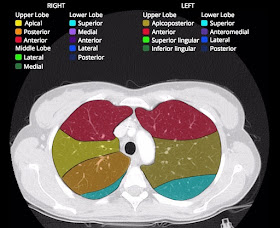

Chụp cắt lớp vi tính (CLVT) phổi và lồng ngực đánh giá được tình trạng bệnh lý của xương sườn, màng phổi, nhu mô phổi, phế quản, tim, mạch máu, trung thất…. Dựa vào hình ảnh chụp CLVT có thể nhìn thấy những bất thường mà không thể phát hiện dễ trên phim chụp X quang tiêu chuẩn thẳng hoặc nghiêng vì bị các tạng khác chồng lên che khuất.

Để có thể chẩn đoán được cần biết rõ về cấc mốc giải phẫu trên cấc lát cắt.